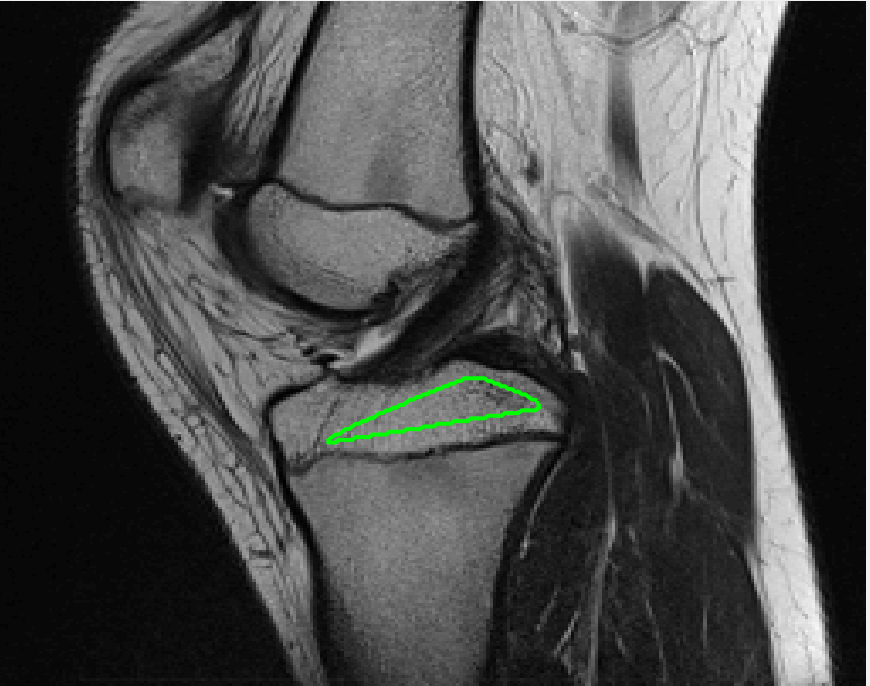

Four sets of test results are shown below. In Test 1 we compare models M1 – M6 to the proposed model M7 for two images which are hard to segment. The first is a CT scan from which we would like to segment the lower portion of the heart, the second is an MRI scan of a knee and we would like to segment the top of the Tibia. See Figure 9 for the test images and the marker sets used in the experiments. In Test 2 we will review the sensitivity of the proposed model to the main parameters. In Test 3 we will give several results achieved by the model using marker and anti-marker sets. In Test 4 we show the initialisation independence and marker independence of the Geodesic Model on real images.

In this test we give the segmentation results for models M1 – M7 for the two challenging test images shown in Figure 9. The marker and anti-marker sets used in the experiments are also shown in this figure. After extensive parameter tuning, the best final segmentation results for each of the models are shown in Figures 10 and 11. For M1 – M4 we obtain incorrect segmentations in both cases. In particular, the results of M2 and M4 are interesting as the former gives poor results for both images, and the latter gives a reasonable result for Test Image 1 and a poor result for Test Image 2. In the case of M2, the regularisation term includes the edge detector and the distance penalty term (see (4)). It is precisely this which permits the poor result in Figures 10(b) and 11(b) as the edge detector is zero along the contour and the fitting terms are satisfied there (both intensity and area constraints) – the distance term is not large enough to counteract the effect of these. In the case of M4, the distance term and edge detector are separated from the regulariser and are used to weight the Chan-Vese fitting terms (see (9)). The poor segmentation in Figure 11(b) is due to the Chan-Vese terms encouraging segmentation of bright objects (in this case), weighting enforces these terms at all edges in the image and near . In experiments, we find that M4 performs well when the object to segment is of approximately the highest or lowest intensity in the image, however when this is not the case, results tend to be poor. We see that, in both cases, models M5 and M6 give much improved results to M2 and M4 (obtained by incorporating the geodesic distance penalty into each). The proposed Geodesic Model M7 gives an accurate segmentation in both cases. It remains to compare M5, M6 and M7. We see that M5 is a non-convex model (and cannot be made convex [39]), therefore results are initialisation dependent. It also requires one more parameter than M6 and M7, and an accurate set to give a reasonable area constraint in (4). These limitations lead us to conclude M6 and M7 are better choices than M5. In the case of M6, it has the same number of parameters as M7 and gives good results. M6 can be viewed as the model M7 with weighted intensity fitting terms (compare (18) and (30)). Experimentally, we find that the same quality of segmentation result can be achieved with both models generally, however M6 is more parameter sensitive than M7. This can be seen in the parameter map in Figure 12 with M7 giving an accurate result for a wider range of parameters than M6. To show the improvement of M7 over previous models, we also give an image in Figure 13 which can be accurately segmented with M7 but the correct result is never achieved with M6 (or M3). Therefore we find that M7 outperforms all other models tested M1 – M6.

Test 3 – Further Results from the Geodesic Model M7. In this test we give some medical segmentation results obtained using the Geodesic Model M7. The results are shown in Figure 14. In the final two columns we use anti-markers to demonstrate how to overcome blurred edges and low contrast edges in an image. These are challenging and it is pleasing to see the correctly segmented results.

(i) (ii) (iii) (iv) (v)